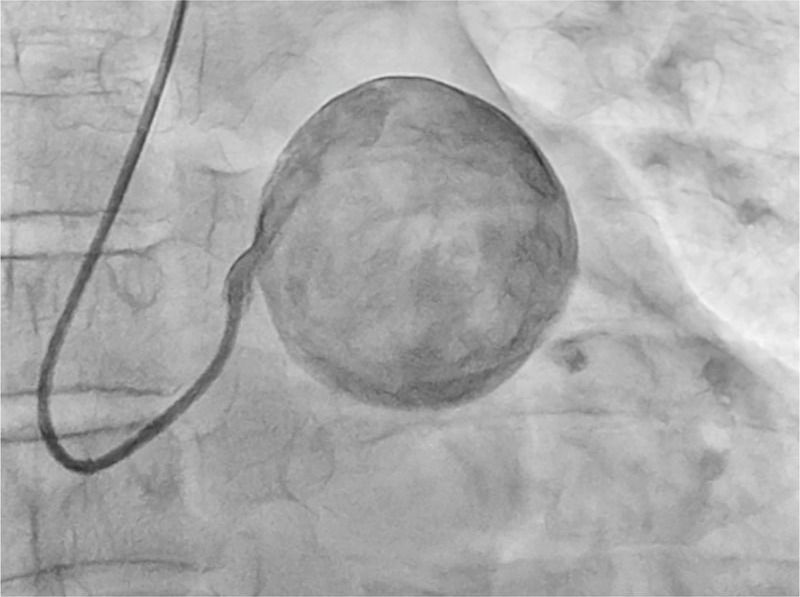

A 49-year-old man with hypertension was referred to our hospital for recurrent angina after receiving recombinant tissue plasminogen activator for acute ST-segment elevation myocardial infarction. His blood pressure was 113/68 mm Hg, and his heart rate was 110 beats per minute. An electrocardiogram showed a right bundle-branch block and ST-segment elevation in the anterolateral leads. The troponin I level was 164 ng per deciliter (normal level, <0.04). Coronary angiography was performed. The left main coronary artery opened into a large spherical cavity — an aneurysm that measured 69 by 53 mm — that filled with contrast material in a swirling fashion, with slow opacification of the left anterior descending and circumflex arteries. Causes of coronary artery aneurysms include atherosclerosis, vasculitides, connective-tissue disorders, congenital defects, infections, and complications of percutaneous coronary intervention. The patient underwent urgent surgery, but the postoperative course was complicated by cardiogenic shock, and he died the day after surgery.